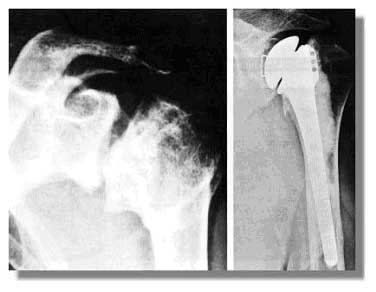

Radiologisch ist neben einer Gelenkspaltverschmälerung und osteophytären Anbauten ein Humeruskopfhochstand sichtbar.

Die Indikation zum endoprothetischen Gelenkersatz ist bei ausgeprägter Schmerzhaftigkeit gegeben. In Abhängigkeit vom Zustand der Pfanne wird diese mit ersetzt oder allein der Humeruskopf.

Der Gelenkersatz ist indiziert, wenn die Gelenkflächen irreparabel zerstört sind durch degenerative, traumatische oder metabolische Ursachen.

Ausgeprägte Omarthrose         Schulterendoprothese

10 Jahre nach intraartikulärer

Trümmerfraktur des Humeruskopfes